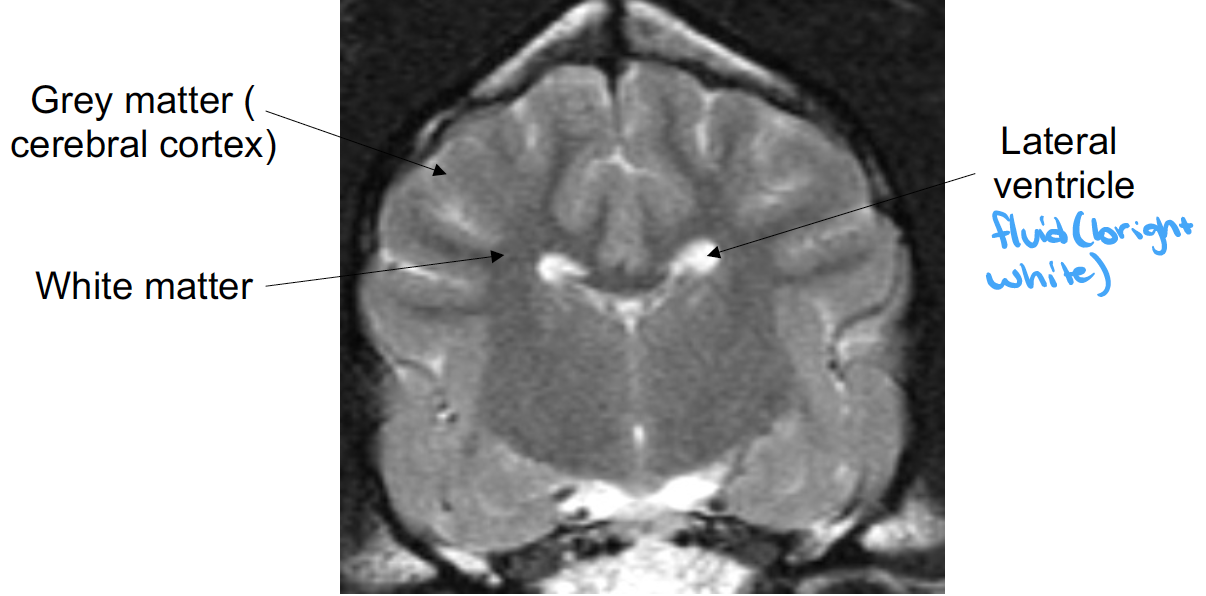

what structures are shown

corpus callosum (left)

internal capsule (right)